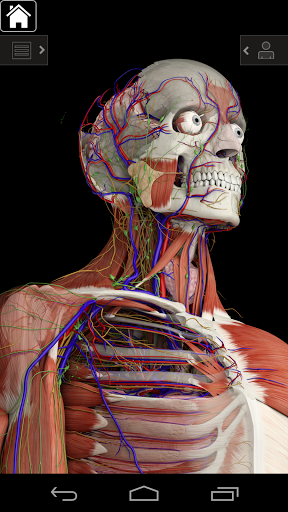

Essential Anatomy 3 represents the latest in groundbreaking 3D technology and innovative design. A cutting edge 3D graphics engine, custom built by 3D4Medical from the ground up, powers a highly-detailed anatomical model and delivers outstanding quality graphics that no other competitor can achieve.

The app represents a unique approach to learning general anatomy. The graphics are unparalleled and make learning, through the use of informative content and innovative features, a rich and engaging experience.

Essential Anatomy 3 is responsive, visually stunning and effortless. The app is fully 3D, meaning that you can view any anatomic structure in isolation, as well as from any angle.

---- Over 4,000 highly detailed anatomical structures